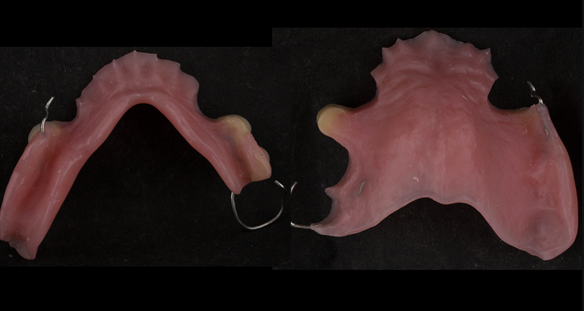

This newsletter describes in step by step detail Angela's transition through immediate partial dentures to crown supported definitive metal based dentures.

The clinical situation and treatment process is shown in detail below with photographs. I (Finlay Sutton) provided the clinical work and Rowan Garstang provided the technical work.